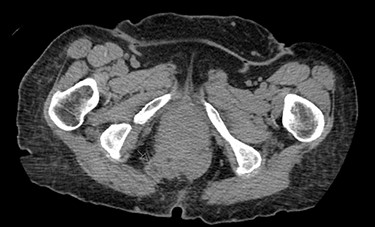

A 62-year-old post-menopausal female presented with worsening fecal urgency, incontinence and a corresponding perianal bulge that was increasing in size over the past 2 years. The patient had a recent history of significant weight loss through diet modification. Medical history was significant for two previous vaginal deliveries, 15-pack per year smoking history, hypothyroidism, hiatal hernia, previous CVA and chronic obstructive pulmonary disease. Fifteen years prior, the patient underwent a total vaginal hysterectomy, including a McCall culdoplasty, anterior and posterior repairs, sacrospinous ligament suspension and tension-free vaginal taping to treat symptomatic cystocele, rectocele and descent of the uterus. A previous computed tomography (CT) demonstrated a heterogeneously enhancing mass extending from the right posterolateral margin of the lower vaginal cuff and perirectal region into the ischioanal fossa, suggestive of, but not definite for a soft tissue mass (Fig. 1). Upon clinical exam, the patient was noted to have a defect in the right levator muscles complex with complete herniation of her rectum through this defect. This hernia created pocking of the stool and difficulties with stool emptying. In addition, the patient had to adjust her sitting position to avoid unwanted stool leakage as a result of spontaneous hernia reduction. The patient was offered an abdominoperineal resection; however, discussion of laparoscopic interventions with the DaVinci robot quickly became the best option for repair. Informed consent was obtained for robotic repair, and routine preoperative colonoscopy was performed.

Once the hernia was completely reduced, the hernia sac was resected. The muscular defect of the pelvic floor was delineated. The pelvic floor was reconstructed, and the muscular defect was reapproximated from lateral to medial using 3-0 V-Loc running sutures in a tension-free manner. An 8 × 8 cm synthetic bioabsorbable Phasix mesh was used to reinforce the repair (Fig. 3). To prevent the rectum from falling back into the pelvis, a suture rectopexy was performed in the traditional fashion by clearing the sacral promontory from overlying soft tissue, exposing the periosteum of the sacral promontory and using silk sutures to attach the rectum to the sacrum. The pelvis was reperitonealized using running 3-0 V Loc absorbable sutures. Post-operatively, the patient had return of bowel function, adequate pain control, tolerated a soft diet and was discharged after 2 days. The patient had significant improvement in her fecal incontinence at her 4-week follow up visit, and post-operative CT demonstrated resolution of the hernia (Fig. 4).

Post-operative CT demonstrating mild fluid in pelvis and resolution of the hernia (black arrow).